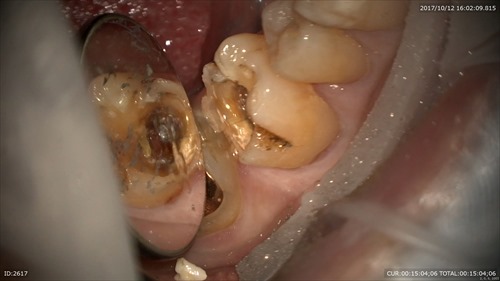

さて今日は前回右下の重症のむし歯を治療、型取りし本日セラミックのセットだった症例です。

主訴:右下取れた。痛い。

大変お辛そうでした。銀歯の恐ろしさが顕著に表れていますね。

むし歯でなくなった部位を補強して。精密な型取り。とにかく丁寧に。